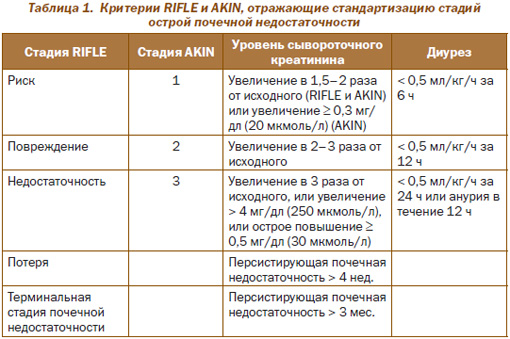

В 2002 г. были предложены временные критерии RIFLE для определения ОПП и его стадий. Аббревиатура RIFLE обозначает три градации ОПП по увеличению тяжести острой почечной дисфункции (Risk — риск; Injury — повреждение; Failure — недостаточность; соответственно R, I и F) на основании оценки динамических изменений уровней креатинина сыворотки, а также двух критериев (Loss — потеря и End-stage renal disease — терминальная стадия почечной недостаточности (ТСПН); соответственно L и E) на основании оценки продолжительности потери почечной функции. Термин Loss (потеря) характеризует наличие персистирующей почечной недостаточности более 4 нед., а термин End-stage renal disease — персистирующую более 3 мес. почечную недостаточность.

Рабочая группа AKIN в 2005 г. определила ОПП как снижение функции почек, при котором отмечают не более чем за 48 часов абсолютное увеличение сывороточного креатинина на 0,3 мг/дл (25 мкмоль/л) или более и относительное увеличение сывороточного креатинина на 50 % и более; или документированная олигурия — менее 0,5 мл/кг/час более чем в течение 6 часов, несмотря на адекватное восполнение жидкости.

В табл. 1 представлены критерии RIFLE и AKIN, отражающие стандартизацию номенклатуры ОПП и ее зависимость от уровней креатинина сыворотки и минутного диуреза.